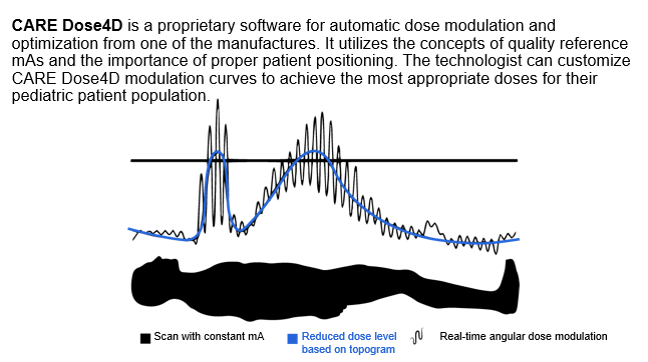

Dose Modulation Techniques

Radiation exposure to the patient has become a concern for the radiologist in the multidetector computed tomography (CT) era. With the introduction of faster multidetector CT scanners, various techniques have been developed to reduce the radiation dose to the patient; one method is automatic exposure control (AEC).

Let’s look at the various dose modulation techniques that are available that help reduces patient dose. CARE Dose 4D (Siemens) assesses the size of the patient cross-section being scanned and adjusts tube current relative to the reference effective milliamperage. It aims to provide adequate image noise, which varies depending on the size of the patient. This system operates on the principle that different-sized patients require different levels of noise to maintain adequate image quality.